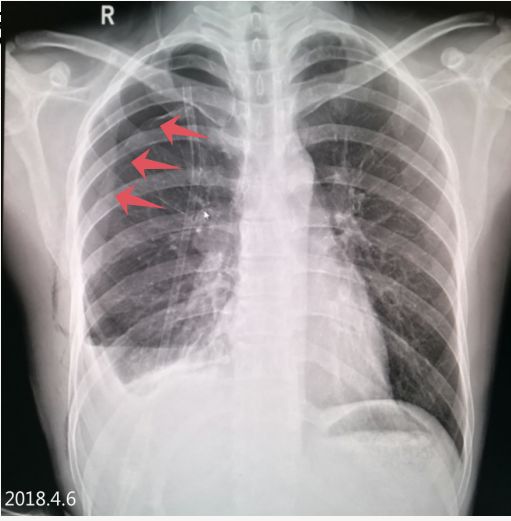

2018.4.1 患者复查X线图像

患者右肺气胸复查所见:右侧肺野外带(约占肺野4/5)见带状异常透亮无肺纹理区,内侧缘可见发线状被压缩肺组织外缘,被压缩约75%以上,内可见引流管置入影。 右侧胸壁可见气体影。

2018.4.6 气胸复张,右下肺见液平面